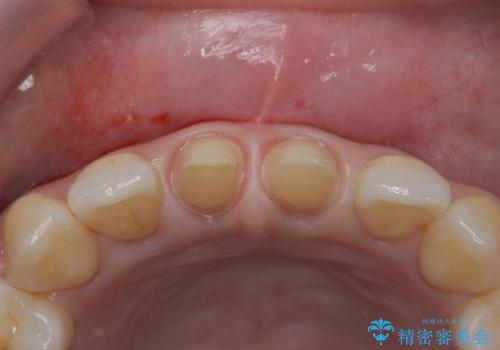

- 前歯の審美性改善と、軽度のがたつきを主訴に来院された患者様です。

マウスピース矯正を行った後、かぶせ物で審美性を改善していきます。